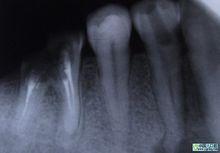

尖周炎症

由於牙根的牙髓組織發炎,引起牙根尖組織病變,如根尖牙周膜腔增寬、根尖囊腫等病變均可在牙片上顯示出來。尖周炎症作牙片檢查的臨床意義有:①了解病牙根管情況:如根管數目、粗細、彎曲度以及有無鈣化、有無內吸收等情況。②幫助確定病牙:如兩牙之間的瘺管插入牙膠尖作牙片檢查,可以顯示牙膠尖偏於某一牙齒。③檢查治療情況:如牙片顯示根管充填是否到底或有無超填。